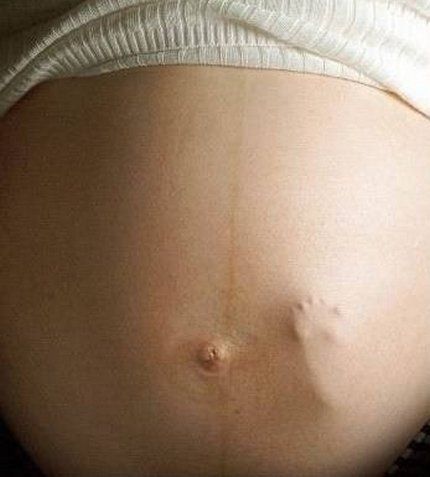

Сила шевелений увеличивается с развитием плода. Сначала они совсем незаметны, далее их начинает ощущать мама (в это время они заметны только для нее). Только потом они становятся настолько сильными, что каждый член семьи, приложив руку к животику, может их почувствовать. В некоторых случаях они проявляются настолько сильно, что их можно даже увидеть.

На большом сроке толчки малыша можно даже увидеть